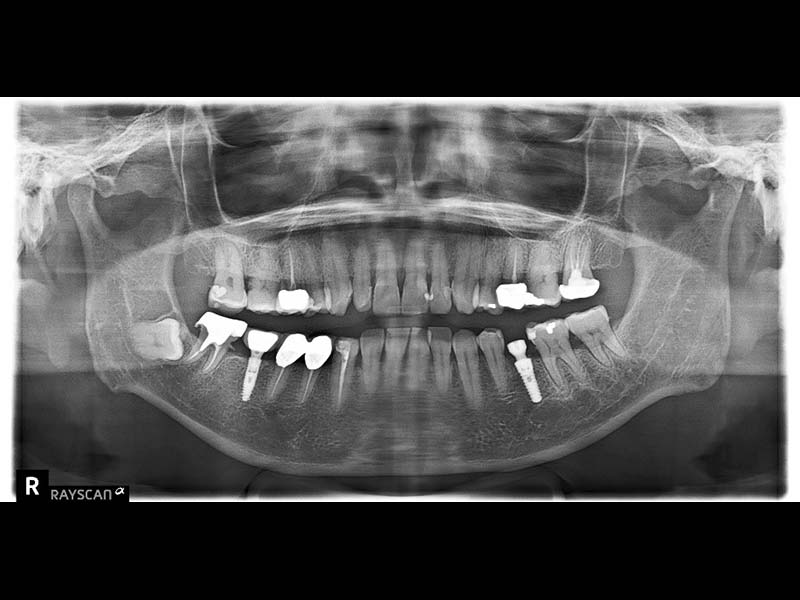

拍攝電腦斷層影像和口腔口掃並製作治療計畫

使用數位手術導板精確定位植體位置,確保角度與深度正確,提升植牙成功率